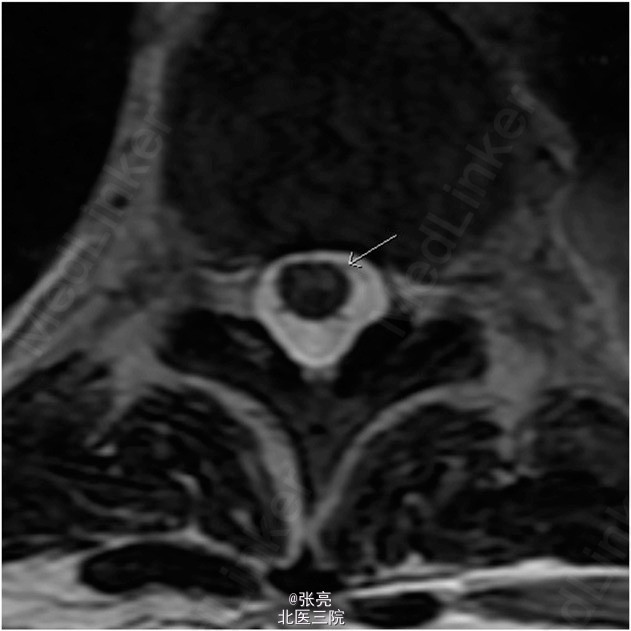

胸腔镜活检确诊为恶性胸膜间皮瘤。患者接受了四个疗程的化疗(顺铂/陪美曲塞),影像学随访显示肿瘤体积逐步缩小。超声引导内镜针吸活检纵隔淋巴结提示无转移。患者一般状态及心肺储备良好。故决定行胸膜外全肺切除术。 顺利在左侧脊柱旁T5到T6节段水平植入导管。给予患者双腔气管内插管,桡动脉和中心静脉置管。患者取右侧卧位,取左侧后外侧切口。肿瘤超出了胸膜覆盖范围,广泛侵犯主动脉周围,但主动脉和肿瘤之间界线清楚。 胸膜外全肺切除术进展顺利,整块切除了受累肺组织、纵隔淋巴结、左侧膈肌和同侧受累的局部心包膜。对T3到T6节段水平的同侧上段胸椎节段动脉进行缝合结扎及电凝切断。相应节段平面和神经管无活动性出血。 给予2 mm的聚四氟乙烯(GROE-TEX)补片修补缺损的膈肌和心包。止血良好。总出血量估计在1300 ml,输注5个单位的浓缩红细胞。术后患者转入ICU,给予小剂量0.5 mcg/kg/min的去氧肾上腺素维持血压。 到达ICU时,患者血流动力学稳定,神经功能完整。手术当晚,患者经历了两次短暂的低血压过程,每次持续不到1min,收缩压降低至60-70 mm Hg。给予输液和调整升压药剂量好有效维持血压。 第二天早晨,护士发现患者双下肢不能活动。体格检查发现双下肢瘫痪,感觉保留。MRI提示,脊髓中枢T5到T12节段水平T2异常高信号,无脊髓硬膜外血肿或脊髓压迫。这些表现与脊髓缺血相一致。 立刻给予患者改善脊髓灌注的标准治疗方案。维持平均动脉压在80mmHg,麻醉师行腰大池引流,降低脑脊液压力至10cmH2O以下。在接下来的2周中,患者下肢运动功能略有改善。但功能上仍截瘫,有大小便失禁。 术后17天,患者转入康复医院接受进一步治疗。

胸膜外全肺切除术有许多并发症,但就作者所知及文献回顾,这是首次术后出现截瘫的报道。开胸术后截瘫的报道一般与局部硬膜外出血所致脊髓压迫或由于止血剂造成的节段椎孔压缩导致的脊髓节段压迫相关。 将肿瘤从后纵隔和胸主动脉行钝性分离,可导致节段动脉或结扎部位撕裂。脊髓灌注取决于对侧完整的节段动脉血供和低位胸椎水平Adamkiewicz动脉的完整。脊髓前角缺血好发部位是在T9到T12节段水平,往往是由于Adamkiewicz动脉区域性缺血所造成。 本文报道了一个罕见的高位脊髓前角缺血,根据MRI推测很可能是由于脊髓中段血管解剖变异所造成。虽然患者术后经历了两次短暂的低血压发生,但是脊髓灌注不良才是造成患者术后截瘫的最可能原因。 对于此类患者需关注这一之前未报道的罕见并发症。应告知患者及其家属这一重要并发症及其可能的风险。